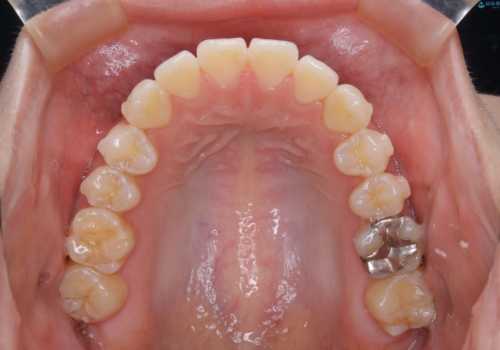

前歯で噛めない:オープンバイト(開咬)を非抜歯インビザラインで治療

オープンバイトの方への治療は、通常抜歯を行いワイヤーによる矯正治療を行うことが多いですが、今回はインビザラインの特性を生かし、非抜歯にて綺麗な歯並びを作ることが出来ました。

舌癖がある方は、歯を内側から押し出す力が日常的に働くため、矯正治療後も歯と歯の隙間が開いてしまうなどの後戻りのリスクが高いことが知られています。舌の正しいポジショニングやお口周りの筋肉のトレーニングを行うことで後戻りのリスクを減らすことが可能です。